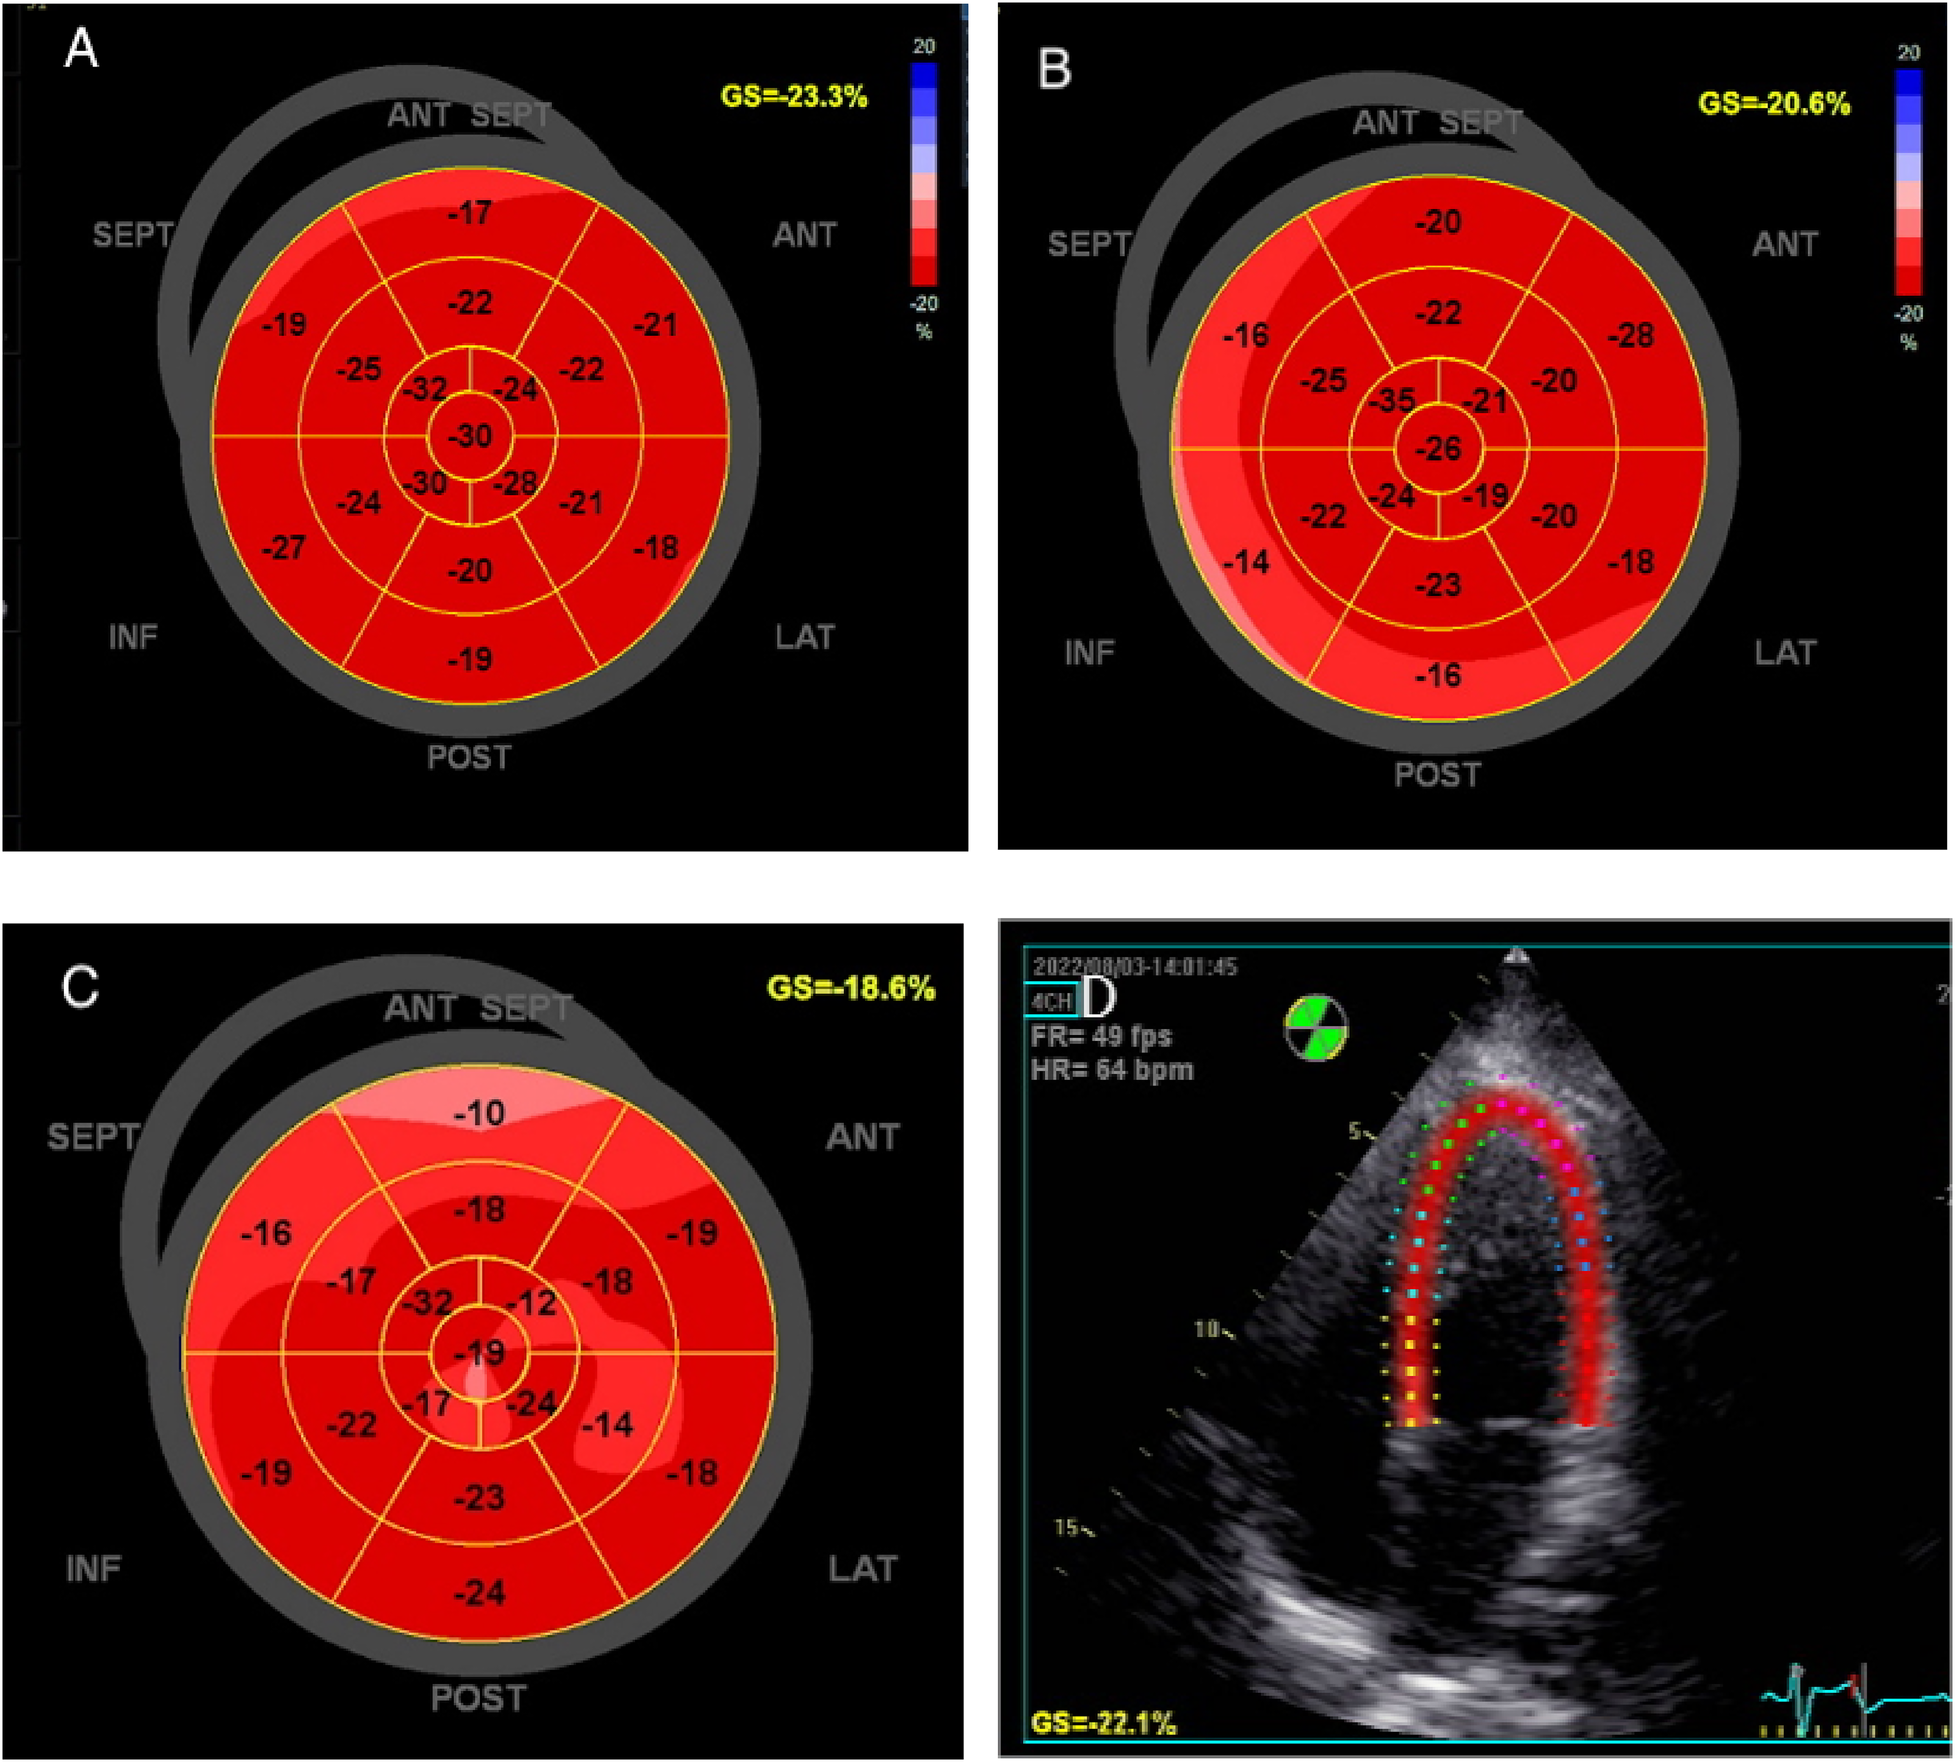

Two-dimensional speckle tracking imaging was used to measure LV GLS. The endocardial and epicardial borders of LV were automatically traced, with appropriate adjustments made to ensure the entire LV wall was encapsulated. LV GLS was then automatically calculated (Figure 2). All the images were acquired by two experienced professional physicians, and another physician, who was blinded to the baseline clinical data, performed the analysis. All parameters were measured for three times and the average value was used for analysis.

Figure 2

The global longitudinal strain of left ventricle was measured by speckle tracking imaging in the same patient. (A) early pregnancy, (B) middle pregnancy, (C) late pregnancy, (D) Speckle tracking imaging.